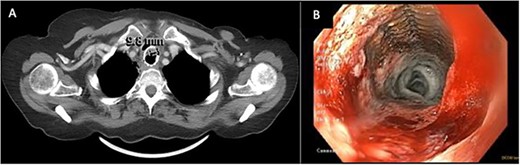

This was the first clear evidence of esophagotracheal communication. Laser debridement was successfully performed again in November 2022, leaving only a small portion where the stent eroded the trachea. On post-bronchoscopy Day 3, the patient reported significant improvements in breathing and energy. Over 6 months, she underwent laser debulking of the tracheal mass twice to manage tumor ingrowth (January and April 2023). Debridement was performed each time using a neodymium-yttrium-aluminum-garnet laser (Fig. 4). Between 380 and 560 joules were delivered to cauterize and debulk the invading tumor. The patient continues to be followed for palliative tumor debulking for ongoing symptom management.

Bronchoscopic view of the endobronchial obstruction. Invasion of the esophageal malignancy can be seen, as well as erosion of the esophageal stent into the lumen of the trachea.